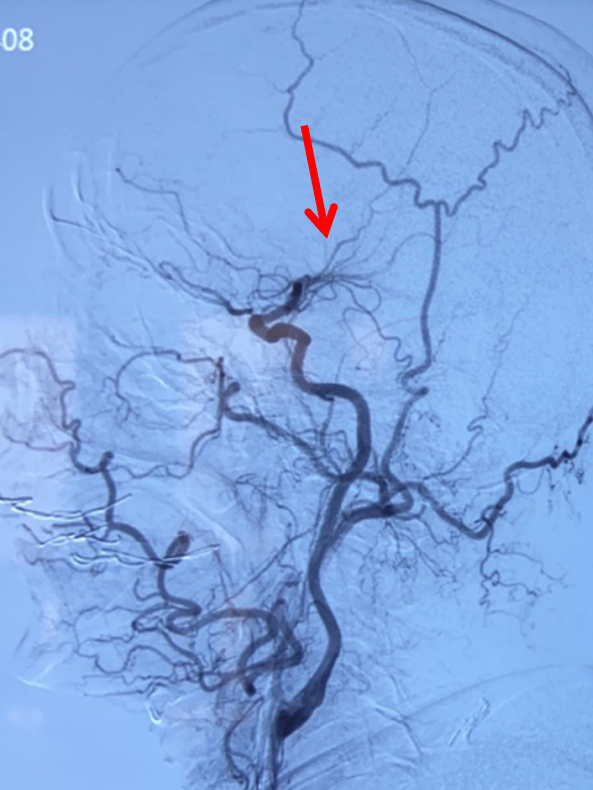

左侧颈总动脉正位造影:双侧大脑前动脉显影,且右侧大脑前动脉通过软膜吻合向右侧大脑中动脉支配区域供血(箭头示)。